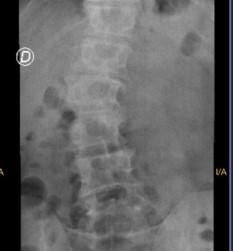

La Cirugía XLIF es una técnica mínimamente invasiva de fusión vertebral que se realiza a través de un acceso lateral, evitando incisiones en la parte anterior o posterior del tronco. Se utilizan instrumentos especializados y monitorización neurológica en tiempo real para proteger estructuras nerviosas y musculares, logrando una fusión vertebral eficaz con menor trauma quirúrgico

Enfermedad degenerativa de disco lumbar

Estenosis del canal lumbar

Spondilolistesis (deslizamiento vertebral)

Escoliosis degenerativa